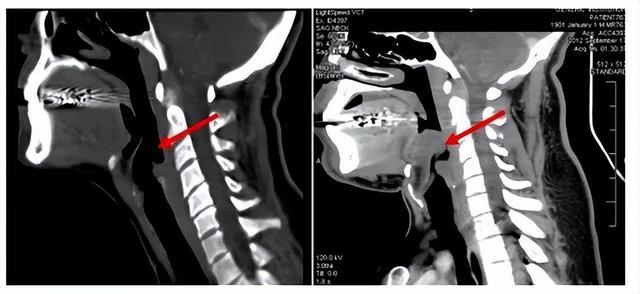

其实你不错把它交融成:喉咙口的一块“小盖子”。

平时呼吸时,它会翻开,让空气获胜相差气谈;吃饭吞咽时,它会盖下来,谨慎食品跑进气管。别看它小,位置却极其重要,简直守着呼吸的“命门”。

问题来了:如若这个“小盖子”倏得发炎、肿胀,会发生什么?

谜底是——它可能像个气球相同迅速饱读起来,径直把气谈堵死。

这即是急性会厌炎最可怕的方位。